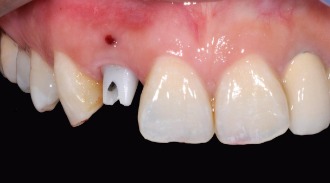

美觀區植牙通常是用於前牙的區域,對於美學較有要求的部位。相較於一般植牙,美觀區植牙更須要注重牙齒美學的考量。另外前牙區的骨壁較薄,缺牙後會有較多的骨質流失,頰側的骨頭容易凹陷。也因此前牙植牙是較具挑戰性的,植牙前各方面的謹慎評估會比一般後牙區植牙來得複雜許多

客製化 二氧化鋯 連接器組合

仿真 植牙用 全瓷牙冠

牙齦塑形來模仿自然牙齒的型態

客製化 二氧化鋯 全瓷連接器,避免牙齦產生黑色陰影